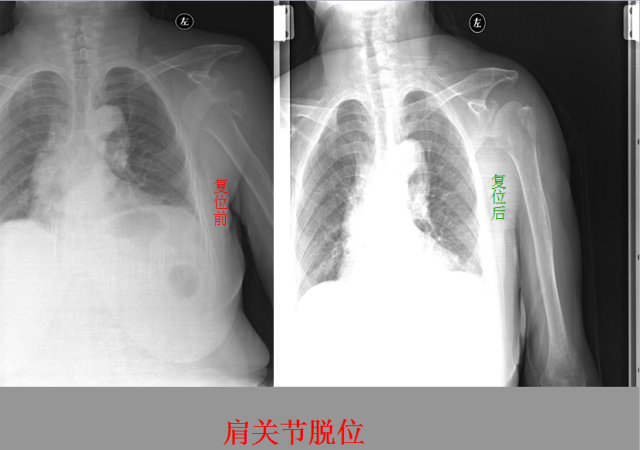

关节脱位篇

02

定义:关节脱位是暴力、关节感染、附近软组织挛缩或先天骨发育障碍造成的关节对位关系部分或完全脱离,即为半脱位或脱位。临床上以创伤性脱位*常见。